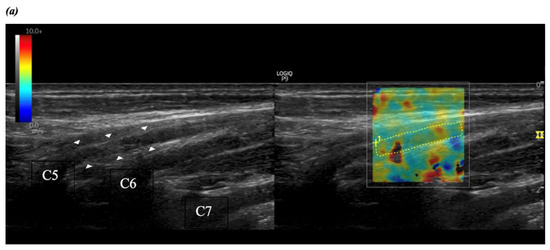

2.2.2. Brachial Plexus Imaging

2.2.3. Shear Wave Elastography and Ultrasound Measurements